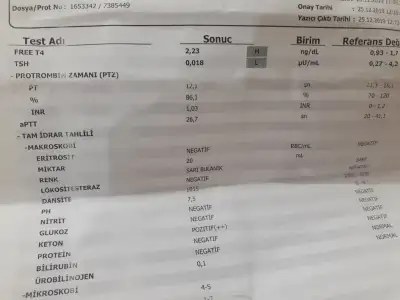

Benimde dusuklerin sebebi tiroid dedi dr ilk günden beri kullanıyorum dahiliyeye yönlendirdi hatta dozu artırdı tabi kafanı karıştırmak için söylemiyorum her drun ne son göre bi bildiği oluyo allahım şifa versin ins